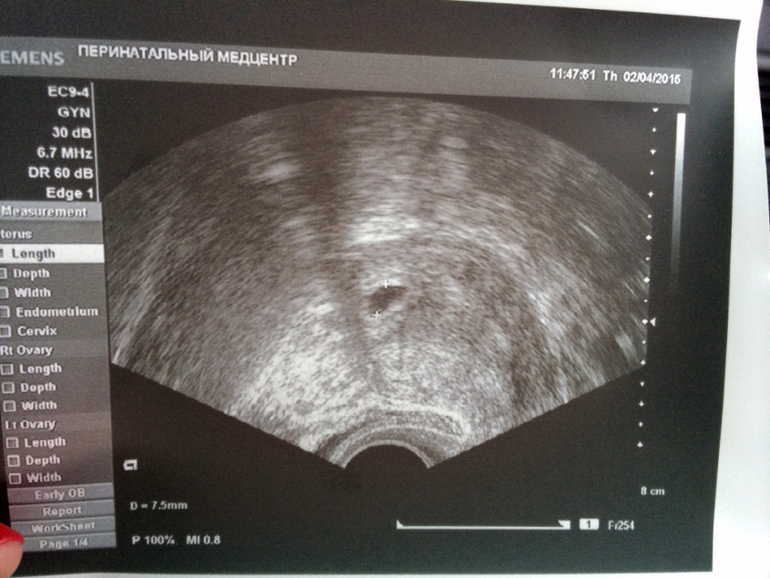

Сегодня 19 дпп одной моей шестидневки 3AC, на узи маточная беременность 4-5 недель, 1 плодное яйцо 7,5 мм, хорион 4,5 мм и желточный мешок 3,1 мм. 18 апреля слушать сердце. Честно сказать, я так долго ждала этого узи, что никаких бурных восторгов или слез на самом узи не было, просто мне было радостно и необычно наблюлать, что теперь все вот так: